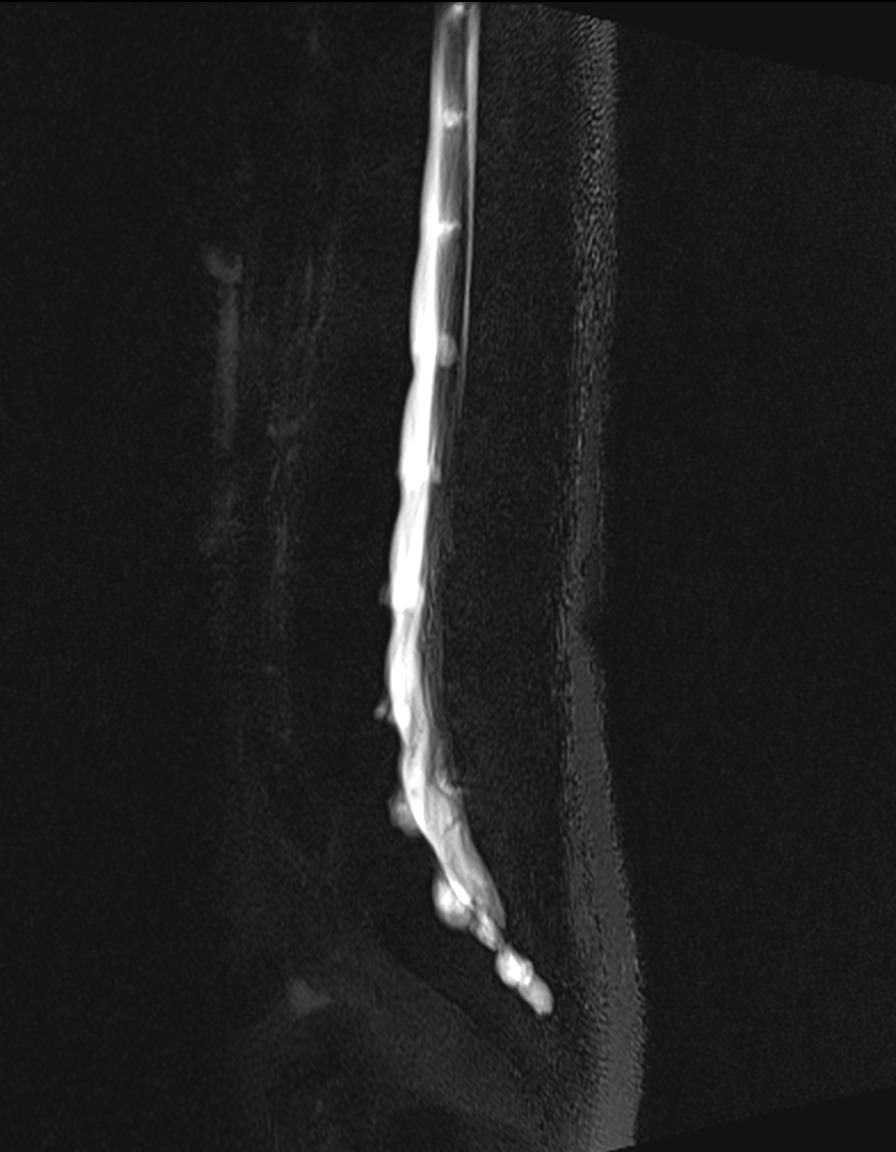

Resonancia Magnética de columna lumbar

“QUISTES PERINEURALES”

Los quistes perineurales son quistes llenos de líquido cefalorraquídeo en las raíces nerviosas, localizados principalmente en la zona sacra de la columna vertebral, aunque pueden encontrarse en cualquier sección de la columna vertebral; pueden causar una radiculopatía progresivamente dolorosa. Las mujeres se ven afectadas con mayor frecuencia que los hombres. Los pacientes con quistes perineurales presentan dolor en la zona de los nervios afectados por el quiste, debilidad muscular, dificultad para sentarse durante periodos prolongados, pérdida de la sensibilidad, pérdida de reflejos, dolor al estornudar o toser, inflamación en la zona sacra, parestesias, dolor de cabeza, ciática, y disfunción intestinal, de vejiga y sexual.

El diagnóstico se basa en la resonancia magnética.